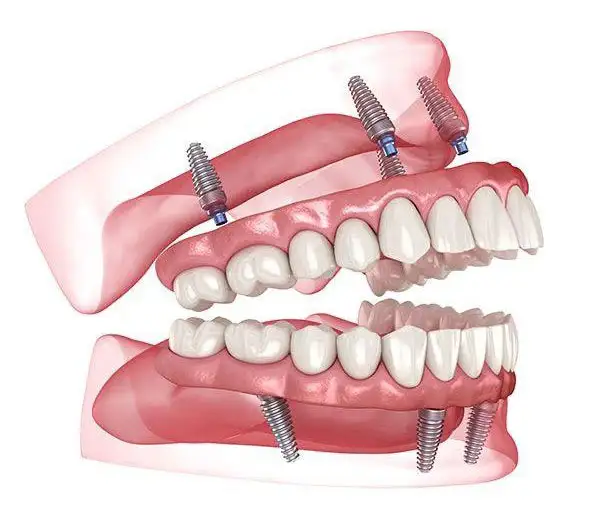

Permanent replacement for missing teeth using high-quality titanium implants that integrate naturally with the jawbone. They function and feel just like natural teeth, allowing you to eat, speak, and smile with complete confidence.

Dental implants preserve jawbone health, prevent facial sagging, and maintain your natural facial structure. They do not affect neighboring teeth and provide a strong, stable, and long-lasting solution for missing teeth. With proper care, implants can last a lifetime, making them the gold standard in modern tooth replacement.